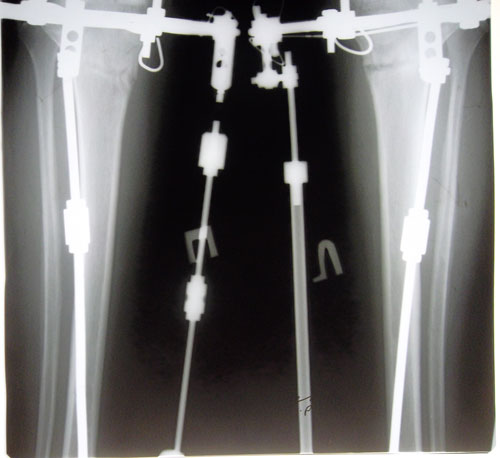

РЕНТГЕН ПЕРЕД СНЯТИЕМ АППАРАТОВ.

SAM_7349.JPG

SAM_7348.JPG